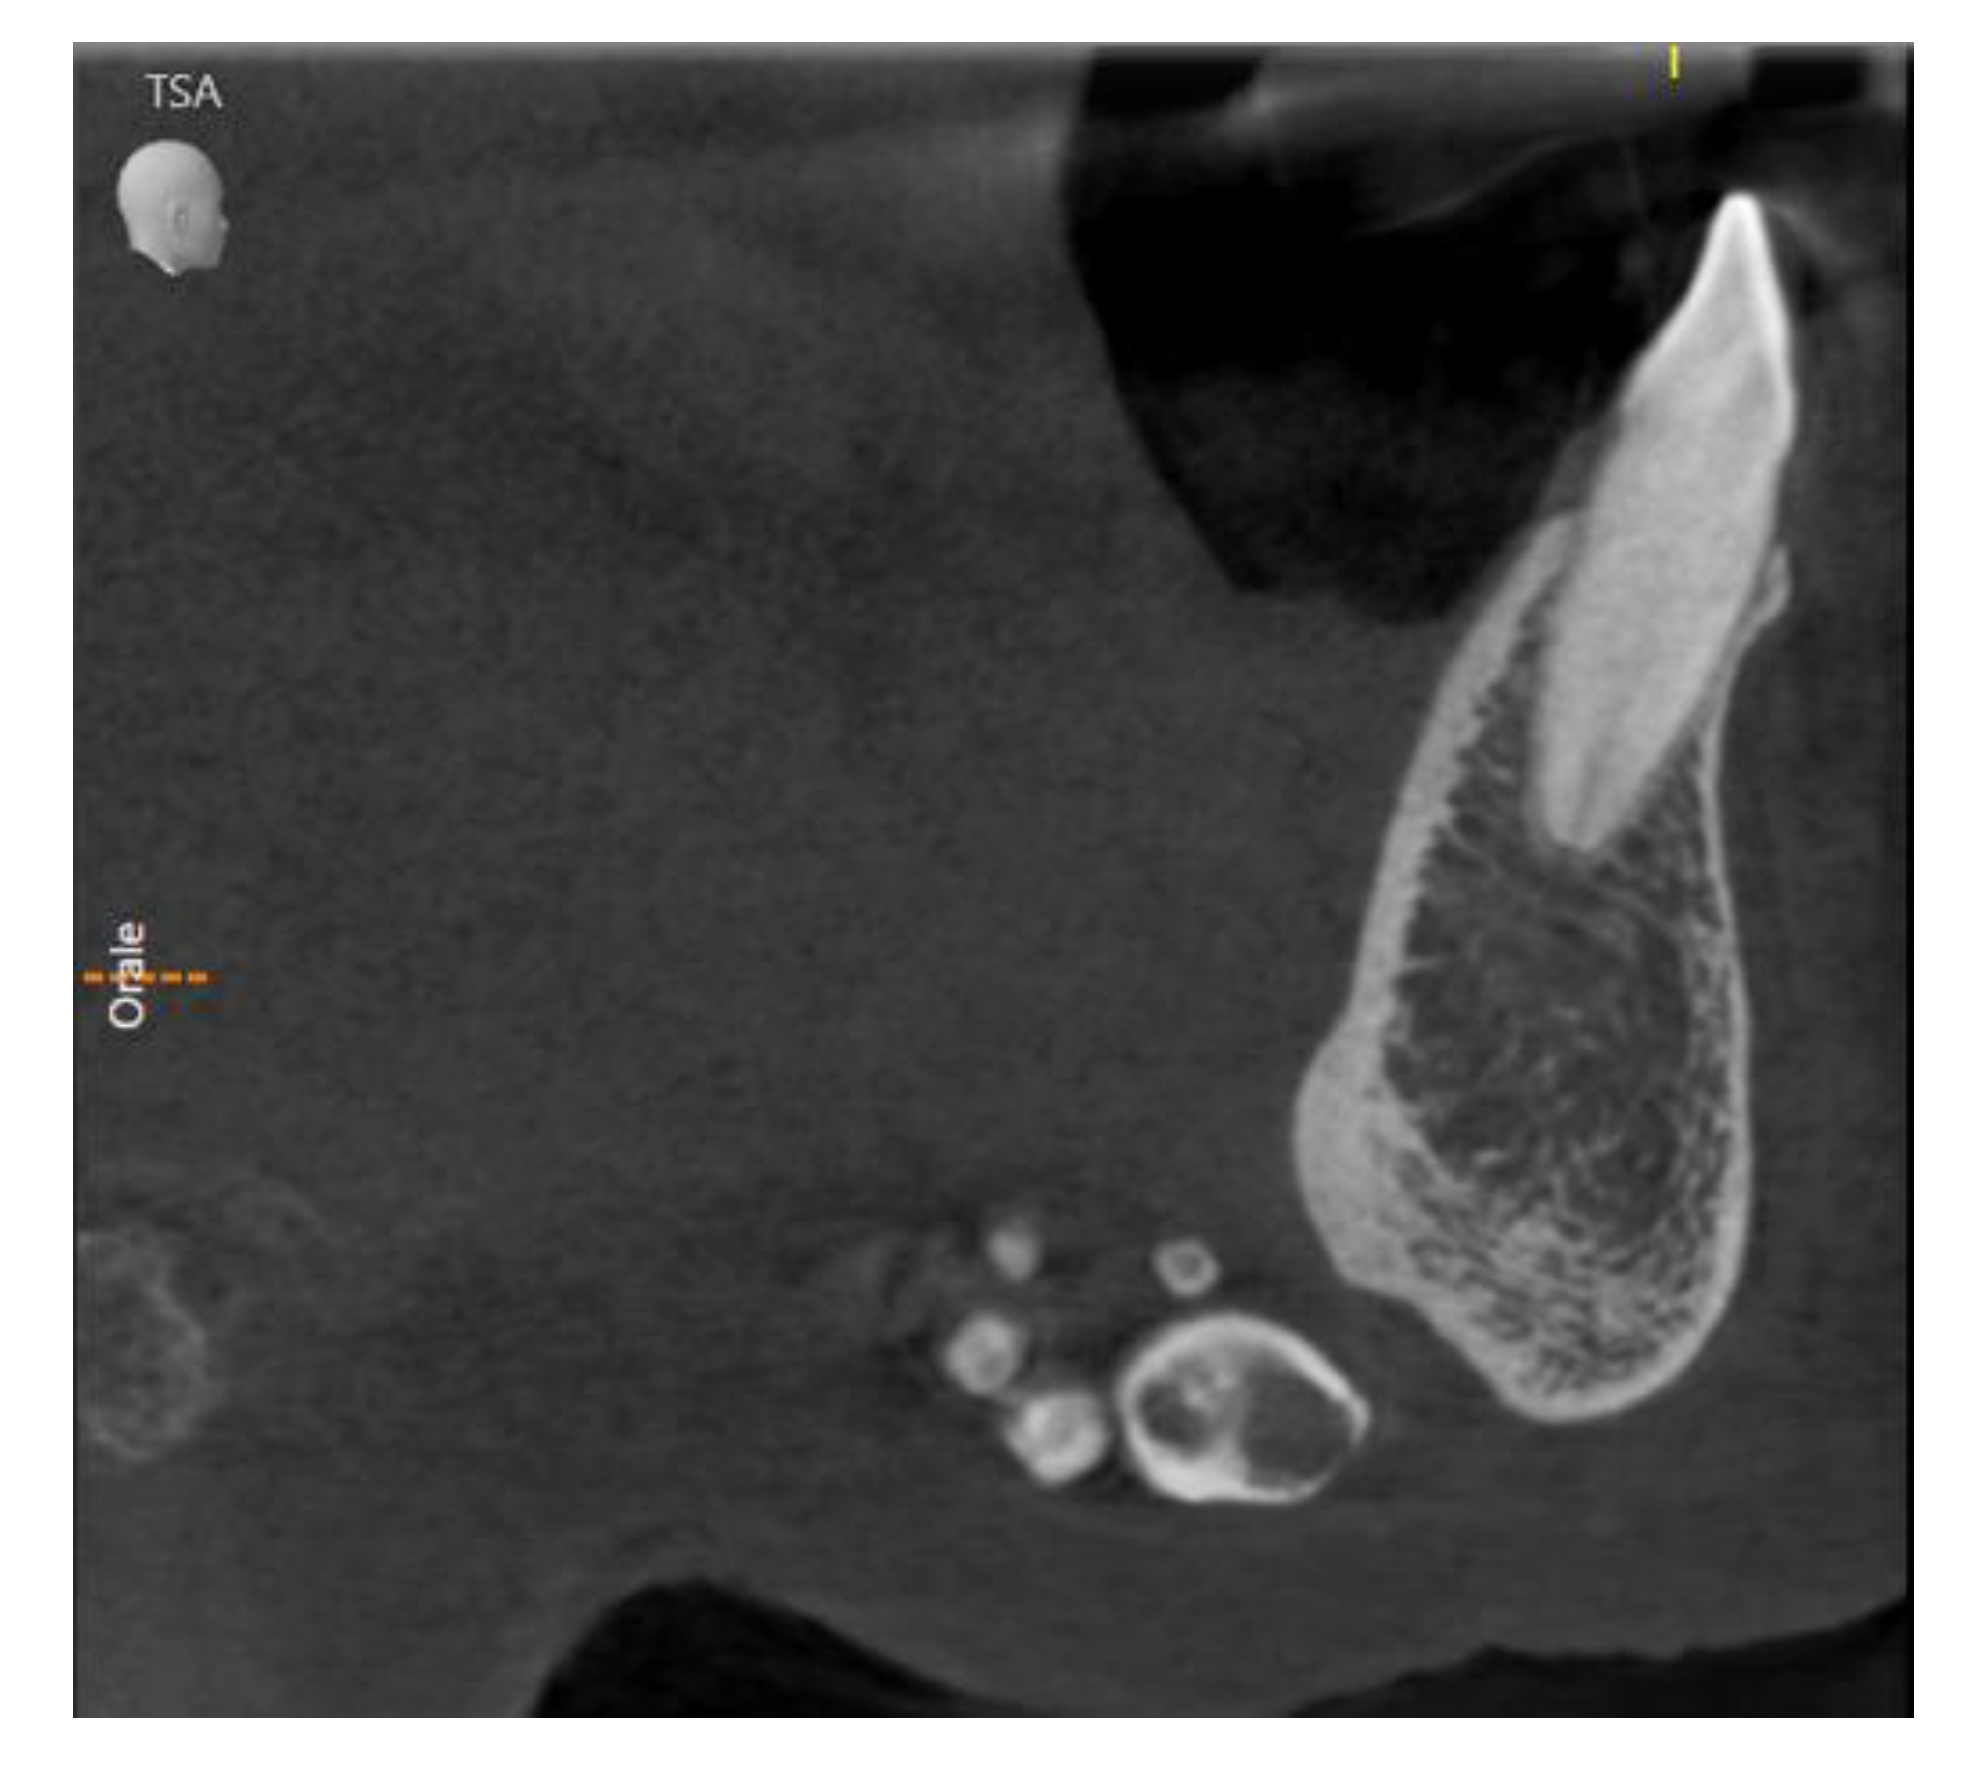

Enigmatic Formations Found in Routine Orthopantomography (OPG) Examinations: A Case Report

2. Case Presentation